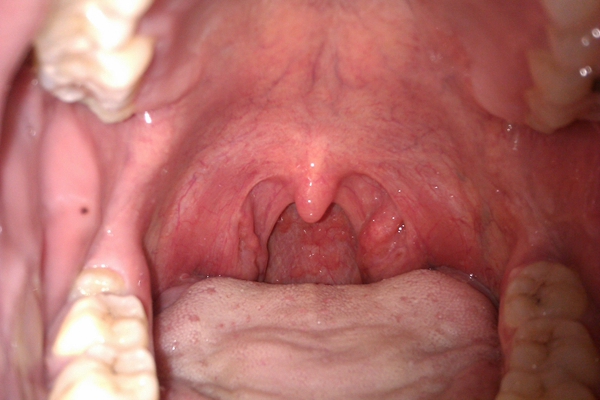

食道炎圖片